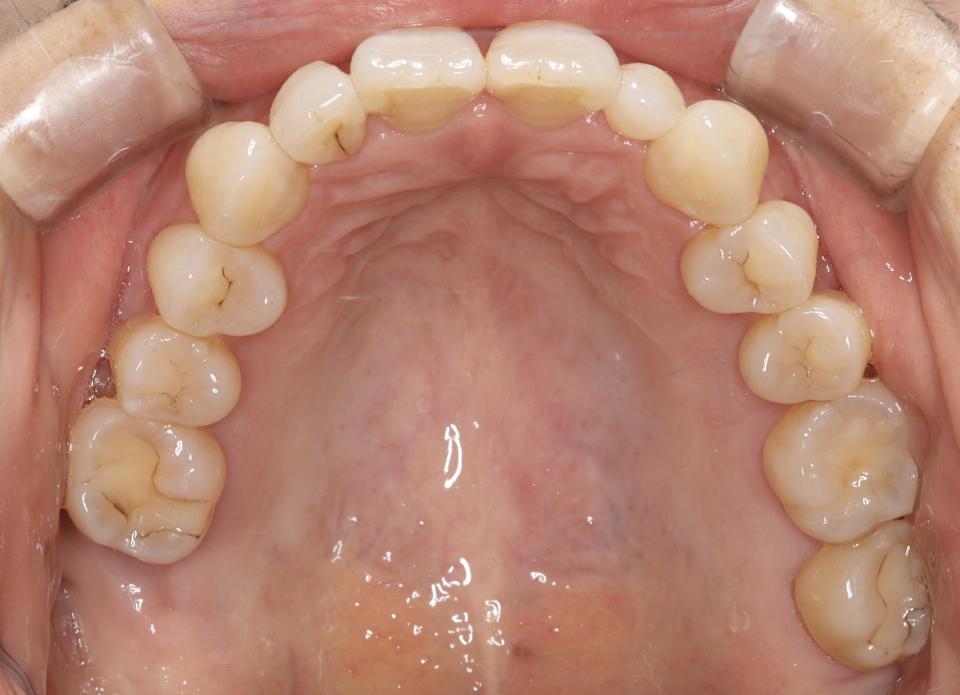

上顎前突(出っ歯)のマウスピース型矯正治療例

矯正治療前

40代女性の患者さんです。

上の前歯が曲がっていることが気になり矯正治療を始めました。

マウスピース型の矯正治療装置を使用し、歯のやすり掛け(IPR)を行いました。